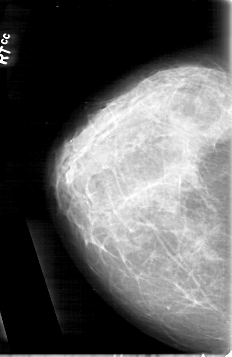

D_4092_1.RIGHT_CC

RIGHT_CC LINES 5341 PIXELS_PER_LINE 3466 BITS_PER_PIXEL 12 RESOLUTION 43.5 NON_OVERLAY